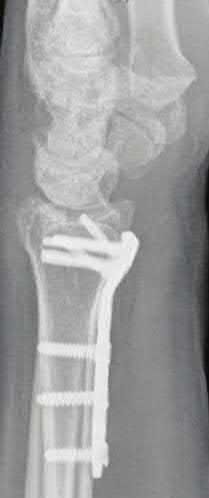

Question 6:

A 45-year-old manual laborer presents with chronic radial-sided wrist pain, recalling a fall on an outstretched hand 5 years ago. Imaging shows a scaphoid nonunion with radioscaphoid and capitolunate arthritis, but the radiolunate joint remains completely preserved. This describes which stage of Scaphoid Nonunion Advanced Collapse (SNAC), and what is a standard surgical option?

Correct Answer: SNAC Stage 3; Four-corner fusion with scaphoid excision

Explanation:

The progression of SNAC wrist is predictable. Stage 1 involves arthritis at the radial styloid; Stage 2 involves the entire radioscaphoid joint; Stage 3 involves the capitolunate joint; Stage 4 involves the radiolunate and/or entire carpus. Because the radiolunate joint is preserved in Stage 3, a four-corner fusion (capitate, hamate, lunate, triquetrum) with scaphoid excision is the standard salvage procedure. Proximal row carpectomy is contraindicated due to capitolunate arthritis.